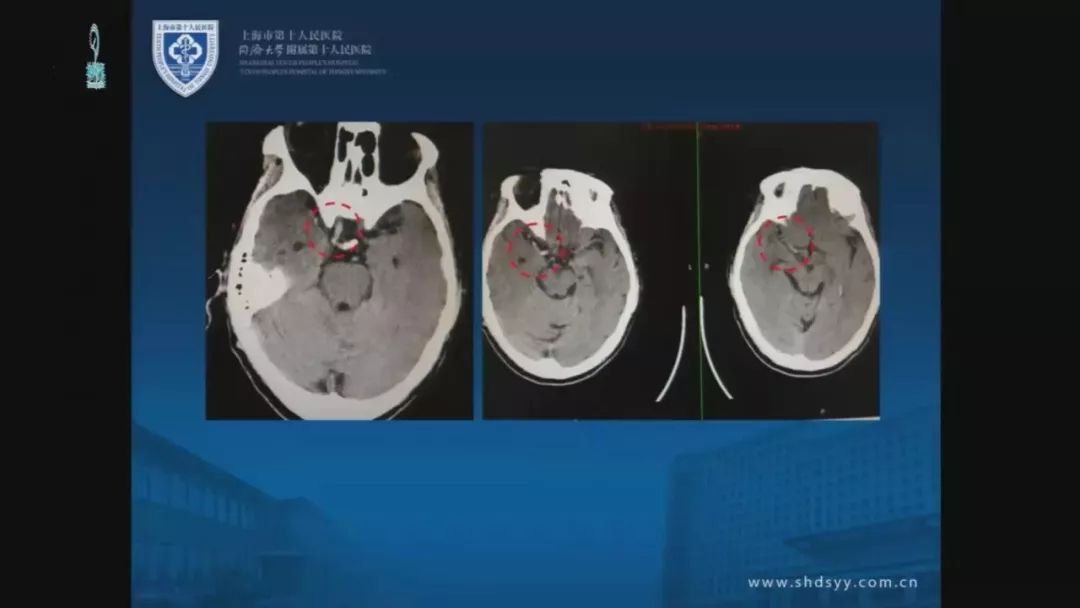

今天为大家分享的是由同济大学附属第十人民医院张全斌教授在第十二届中国医师协会神经外科医师年会上带来的“AIS机械取栓/血流重建的困难与困惑”精彩讲课视频和PPT,欢迎观看!(内容未经讲者审核,不当之处请与我们联系)